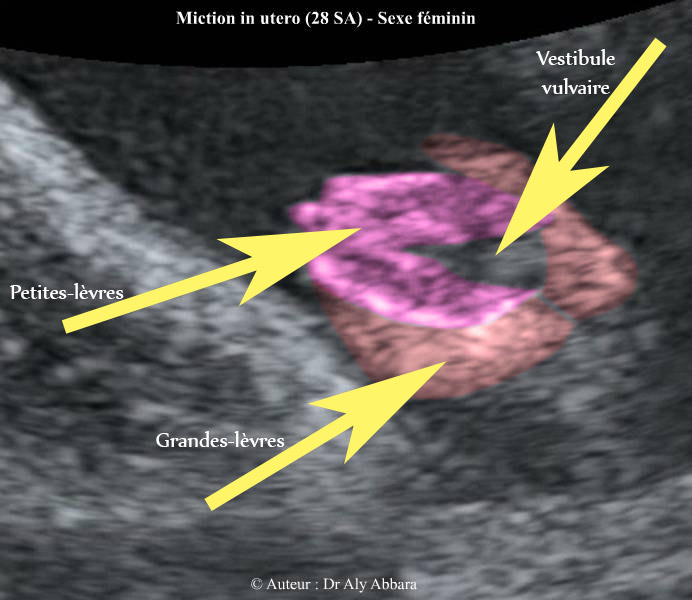

Vulve : 28 SA ; éléments anatomiques

Image échographique montrant une miction urinaire chez un fœtus

du sexe féminin âgé de 28 SA

Image animée montrant les éléments anatomique de la vulve fœtale : vestibule vulvaire, petites lèvres et grandes lèvres) ; image enregistrée au moment de la miction urinaire avec une durée réelle ; elle est caractérisée échographiquement par un jet échogène provenant du vestibule vulvaire.

Auteur : Dr Aly Abbara